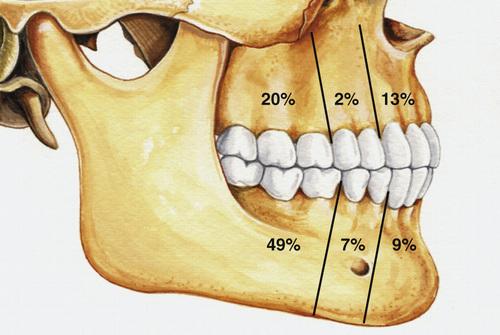

- most often occurs in the mandible (60% to 80%)

Radiographic Features

- well-defined radiolucent area

- large lesions may appear multilocular

- smooth and often corticated margins

- growth in an anteroposterior direction

- may involve an unerupted tooth (25% to 40%)